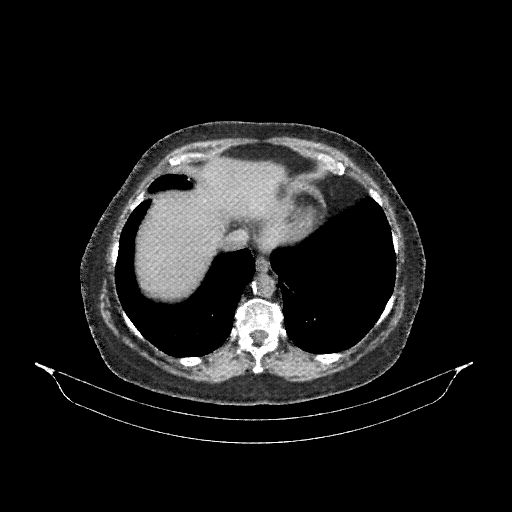

Generated VENOUS CT scan (A→B translation)

Full window (WL 1023.5, WW 4095 β†’ Low βˆ’1024, High +3071)

Actual HU range: [-1024.0, 1188.4]